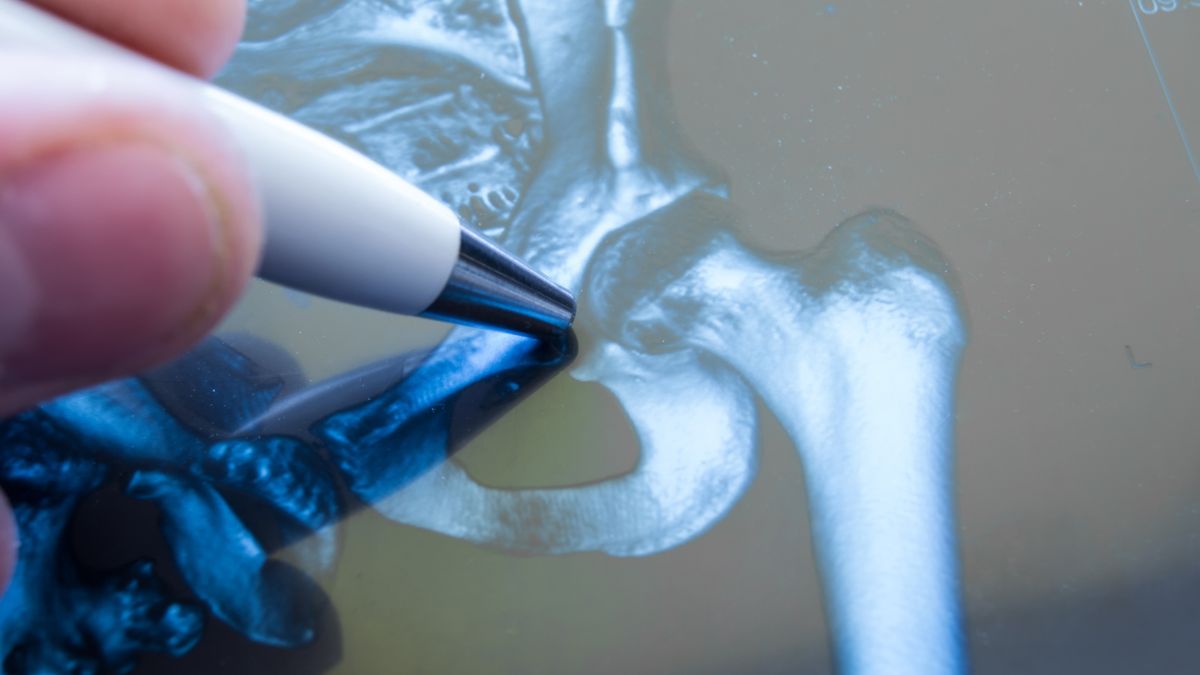

Płyn w stawie biodrowym oznacza najczęściej zapalenie stawu biodrowegoPłyn w stawie biodrowym oznacza najczęściej zapalenie stawu biodrowego

Co oznacza płyn w stawie biodrowym? Najczęściej zapalenie stawu biodrowego. Pod tym pojęciem kryje się grupa chorób wywołana różnymi czynnikami etiologicznymi i mającymi różny przebieg.

Stosowane badania obrazowe to RTG stawu biodrowego i USG. Czasem konieczna jest punkcja stawu biodrowego pod kontrolą USG. Wykonuje się ją, gdy płyn w stawie biodrowym utrzymuje się długotrwale lub istnieje podejrzenie wystąpienia septycznego zapalenia stawu (wskazuje na to mętny płyn w USG, wysokie CRP i PCT).